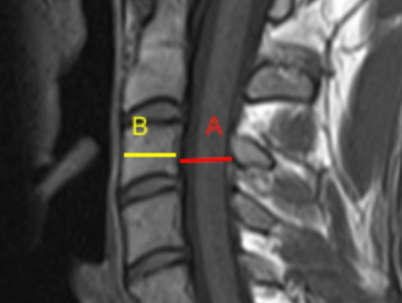

Image Type Cervical Spine X-Ray CT Scan MRI Scan Compression Ratio (AP diameter transverse diameter of cord) Cord Cross-Sectional Area (CSA) Cross-Sectional Canal Area Maximum Spinal Cord Compression Pavlov/Torg (Canal-Body Ratio) Sagittal Canal Diameter Spinal Cord Signal Change - T1 Hypointensity Spinal Cord Signal Change - T2 Hyperintensity (+ number of levels)